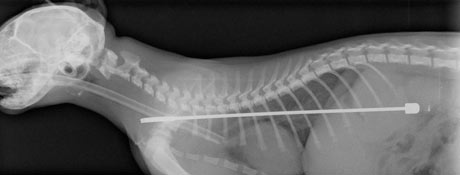

Mintha csak David Cronenberg rendezett volna egy internetes mémet, úgy írta meg a Guardian, hogy Alphie a sheffieldi cica, aki naponta több megbabonázott órát töltött a televízió előtt, egy nap lenyelte a készülék 15 centis antennáját.

Alphie persze azóta már jól van, mint a kép is mutatja, sikerült kioperálni belőle fémdarabot. A sheffieldi állatorvos nem is látott még ilyen esetet, a legközelebbi az volt, amikor egy kutya lenyelt egy sátorpecket.